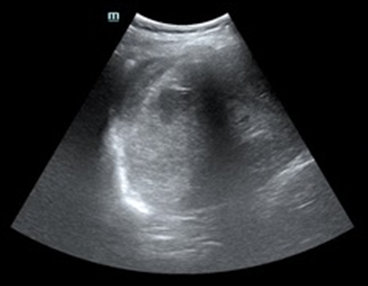

Tras varias horas en observación el paciente comienza con tendencia a la hipotensión. Permanece en observación y monitorización persistiendo hipotensión arterial con buena ventilación bilateral en la auscultación pulmonar. En la exploración abdominal presenta dolor y defensa a la palpación profunda en hipocondrio izquierdo. Se realiza Ecografía clínica a pie de cama del paciente descartando hemoneumotótax y derrame pericárdico; al explorar el abdomen se objetiva líquido libre en espacio de Morrison y eje espleno renal, con imagen compatible con rotura del parénquima esplénico. Gasométricamente se objetiva anemización con caída de cifras de Hb de 15,7 g/dl en análisis inicial a 13,8 g/dl. Se solicitan pruebas cruzadas, se reservan hemoderivados y se contacta con cirugía para traslado del paciente a quirófano.